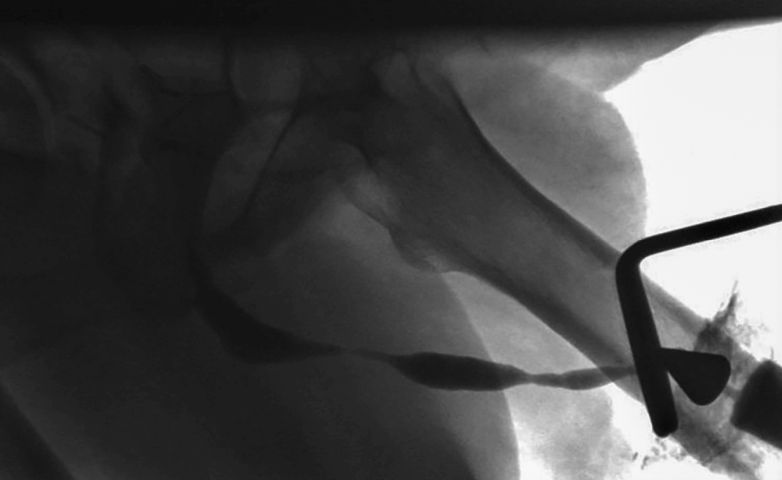

Eine der häufigsten Ursachen für die „Salvage“-Situation im Bereich der Harnröhre ist Hypospadiekorrektur im Kindesalter. In unserer Serie z. B. war diese für 91 % der Fälle verantwortlich. Oft ist die genaue operative Methode, die im Kindesalter verwendet wurde, nicht mehr bekannt. Insofern ist eine korrekte präoperative Beurteilung der gesamten Harnröhre unentbehrlich. Eine mögliche Behaarung der Harnröhrenwand oder multilokuläre Harnrährenstriktur müssen entsprechend bei der Wahl des operativen Verfahrens berücksichtigt werden (▶ Abb. 1, 2).

Jeder Patient erhielt eine standardisierte Diagnostik, die ein Urethrogramm und eine Urethroskopie bzw. eine Sicht-Urethrotomie beinhaltete. Die endoskopische Untersuchung war zum Ausschluss einer behaar-ten Harnröhre oder zusätzlicher Beteiligung der bulbären Harnröhre durch die Striktur und somit zur genauen Therapieplanung unentbehrlich, weil allein ein Miktionscystourethrogramm für die Beurteilung der genauen Strikturlokalisation und -länge nicht ausreichend ist [2].